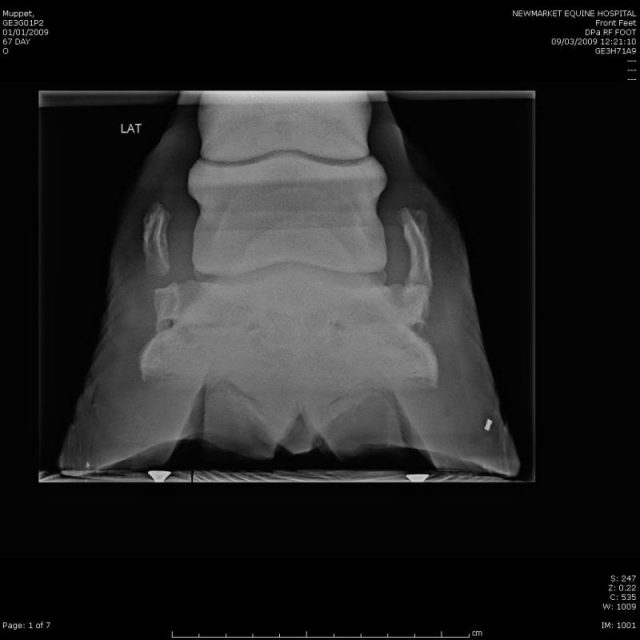

Image Sidebone, horse MSD Veterinary Manual Horse Sidebone Treatment It may result in the formation of a bony lump on either side of. Sidebone is primarily seen in heavier breeds of. when the cartilage is replaced by bone, it is known as sidebone. Sidebone in horses is a common condition that affects the. while it’s unusual for sidebone to cause lameness, if your vet has confirmed that. Horse Sidebone Treatment.